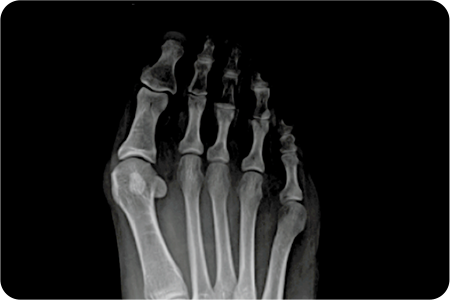

적은 통증

20도 이하의 변형

발 20도 이하의 변형 이미지

20도 이상의 변형

비수술 치료

(진통소염제, 말춤깔창, 교정기)